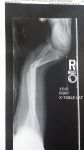

Max's 1st and 2nd injuries = all in 6 months time!

break #2.jpgbreak # 1.jpglittle boy.jpg

Yikes! Max has got me beat!